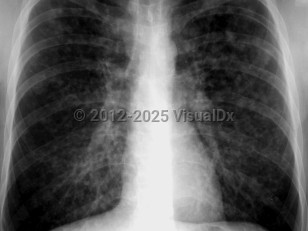

Chest pain, Pleural effusion, 50-59 year old Female

Pleural effusionPleural effusion

Congestive heart failureCongestive heart failure

Pulmonary edema